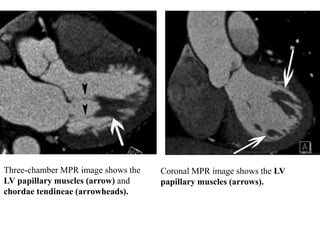

Three-Chamber View.—The three-chamber view is an oblique long-

axis view that optimizes visualization of the LV, LA, aortic root, MV,

and aortic valve.

The three chamber view allows evaluation of the LV outflow tract,

aortic valve, aortic root, and proximal ascending thoracic aorta.

The posteromedial papillary muscles are often seen arising from the LV

free (lateral) wall on this view.

Three-chamber MPR image shows the

LV papillary muscles (arrow) and

chordae tendineae (arrowheads).

Coronal MPR image shows the LV

papillary muscles (arrows).

Horizontal Long-Axis View.—The horizontal long-axis view, or four-

chamber view, is a horizontal plane through the heart that essentially

bisects all four cardiac chambers.

The resultant display readily allows assessment of chamber size and

valve position. The septal, apical, and lateral LV walls can be

simultaneously assessed.

The lateral wall of the LV is normally thin at the apex (typically 1–2

mm), even in abnormally thickened hearts.

Subjective evaluation of AV valvular and ventricular function is usually

also possible in cine mode.

LA size can readily be determined. An area of less than 20 cm2 is

normal, 20–30 cm2 is mildly abnormal, 30–40 cm2 is moderately

abnormal, and greater than 40 cm2 is severely abnormal

Horizontal long-axis MPR image

shows the LV (large black *), RV

(large white *), LA (small black *),

right atrium (RA) (small white *), MV

(black arrow), tricuspid valve (white

arrow), and pericardium (arrowheads).

illustrates calculation of the LA area. The

yellow line drawn along the endocardial

border of the LA creates an irregular

ellipse.